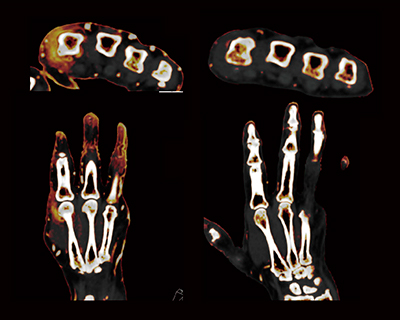

DECTによるヨードマップ画像の利点としては,PsA好発部位であるDIPの画像を鮮明に各指で評価が可能なことである。図2のように,5指すべてに高解像度の矢状断画像を作成でき,炎症の診断が可能である。また,変型が強い関節でも,各関節に対応した横断像を作成して診断することができる(図3)。それによって,PsAの診断がより正確になり,視覚的に治療評価が可能となった。

図2 左1指〜5指のDECTヨードマップの矢状断像